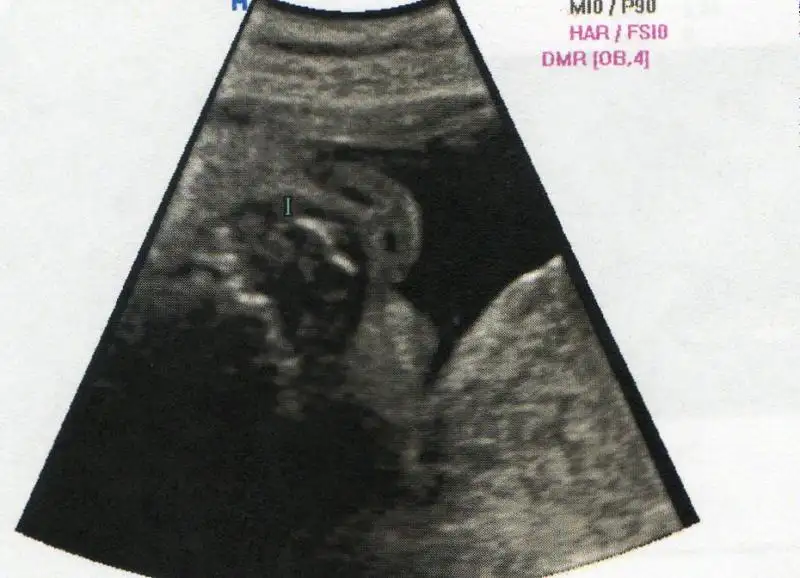

bu arada baharıma bakınnn 3boyutlu resmi :) burnu büyük mü neee